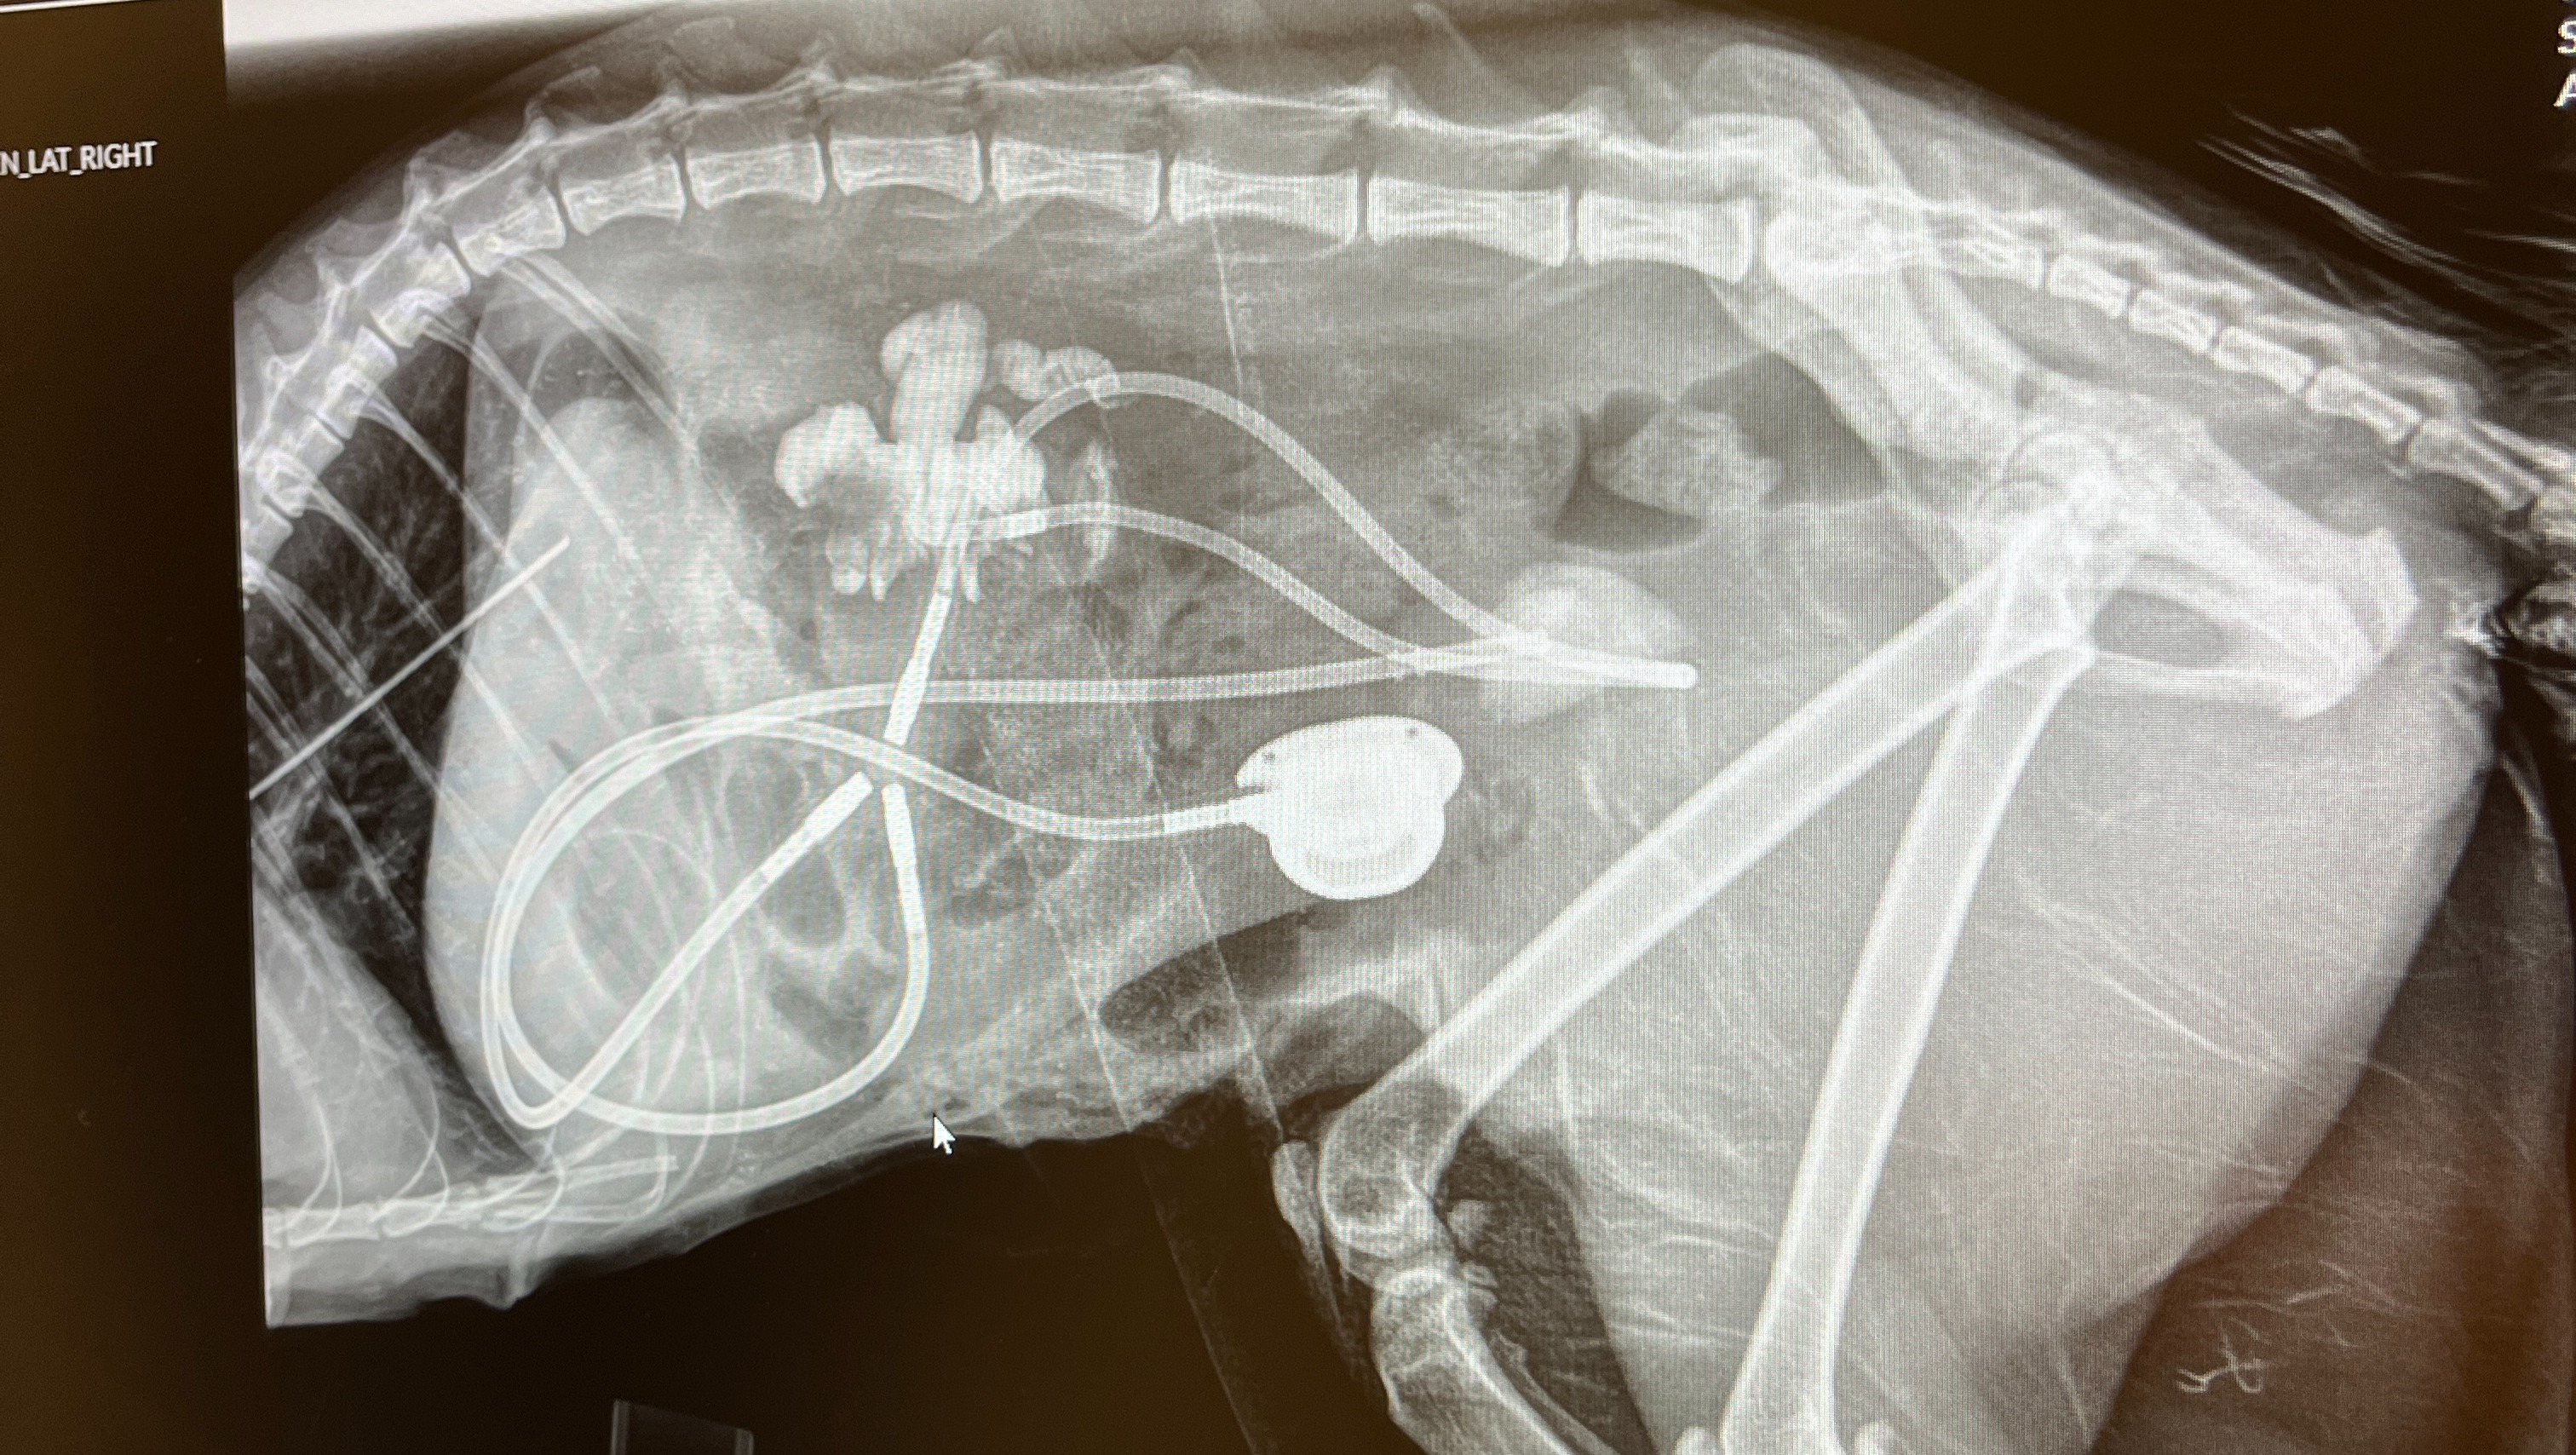

After a weekend stay at the emergency vet, we received a call that they suspected she might have a ureteral obstruction that would require surgery. We took her to the only vet in the area that could see her that day (a 45 minute drive from where we live) and they confirmed what the emergency vet suspected -- RZA had ureteral stones. The only treatment moving forward was subcutaneous ureteral bypass (SUB) surgery, which is a system that bypasses the ureter and diverts urine from the kidney to the bladder. The total cost of just the surgery was around $10,000. After a long discussion with the vet about quality of life and success rates, we decided to move forward with the surgery given that she is so young and otherwise healthy.

The surgery was a success, however not without complications. RZA had a kidney infection that caused the SUB to become clogged the next day requiring another surgery to revise the implant (another $3000). She also became anemic and needed a blood transfusion. Throughout this whole process, the vet assured us that our girl was bright eyed and full of life. We couldn't give up on her after coming this far.

Even with the SUB, RZA will need on-going care. Every 3 or so months we have to take her to get her SUB flushed, a procedure that costs around $500. Additionally, has to be on a special (expensive) kidney diet for the foreseeable future, take various medications, and may need veterinary appointments to receive fluids.